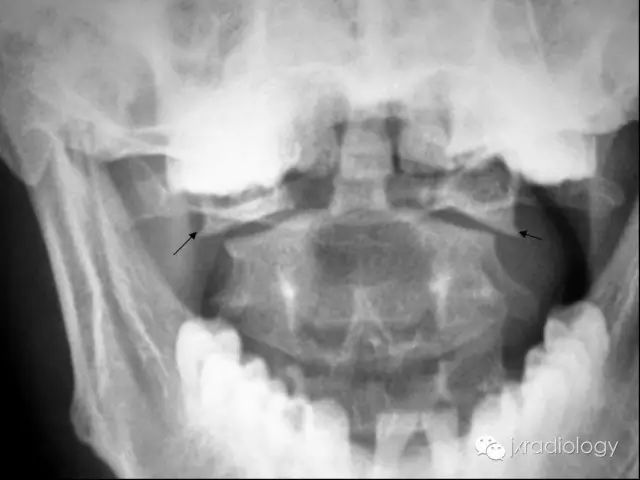

寰椎骨折又名Jefferson骨折(因由Jefferson于1920年首次报道,故此命名)。环形的寰椎遭受轴向压缩和头部向后、下转伸时,暴力经枕骨髁作用于寰椎侧块,并引起寰椎骨环爆裂(散)骨折。寰椎的前弓与后弓双侧骨折,以致侧块被挤压而向四周分离

主要介绍颈椎开口位的X线平片表现:开口位可发现寰椎左右增宽,且与齿突的距离双侧常呈不对称状。如双侧侧方移位总和超过7mm者,则表示寰椎横韧带断裂、寰椎骨折。

正位与齿状突对比似双侧开门样增宽,为此加深记忆,故得此名,如有不妥,敬请谅解(小编)。